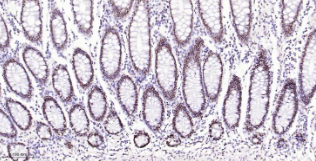

Immunohistochemical analysis of paraffin embedded Human colon tissue slide using IHC0642H (Human p53BP1 Kit).

12 Control slide (Human colon) 1 slide RTU RT